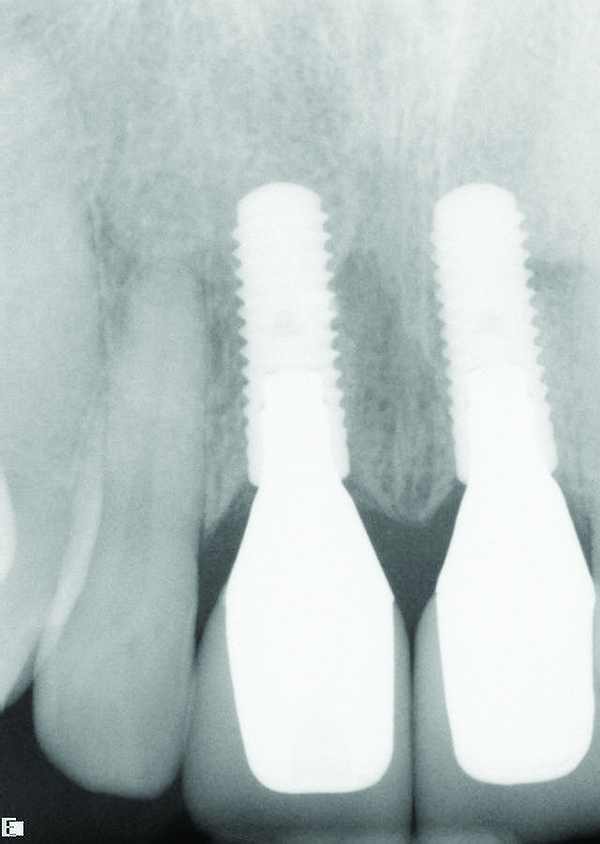

The DICOM (digital imaging and communications in medicine) images are then imported from the CBCT files into one of many commercially available implant-planning software programs. The surgeon and restorative dentist can then collaborate in choosing the precise position, angulation, and depth of implant placement, as well as the implant type, based upon a desired prosthetic outcome. Rosenfeld et al coined the term “collaborative accountability” to describe the pretreatment analysis and subsequent negotiated compromises between surgical and restorative colleagues on implant positioning and restorative design based upon anatomic limitations and the team’s willingness and ability to overcome them.3 Additionally, this pretreatment evaluation is invaluable in creating realistic patient expectations. Figure 1 through Figure 6 demonstrate a case showing 3-dimensional (3-D) presurgical planning, radiographic evidence of the plan’s execution, and 2-year follow-up. As a result of 3-D planning and subsequent guided implant surgery, the patient wound up with a pleasing, nature-like esthetic outcome (Figure 5).

Fig 4. Radiograph taken on the day of delivery of the final implant-supported restorations, 3 months after implant placement.

Figure 4

Fig 6. Radiograph of crown Nos. 8 and 9, 2 years after implant placement.

Figure 6